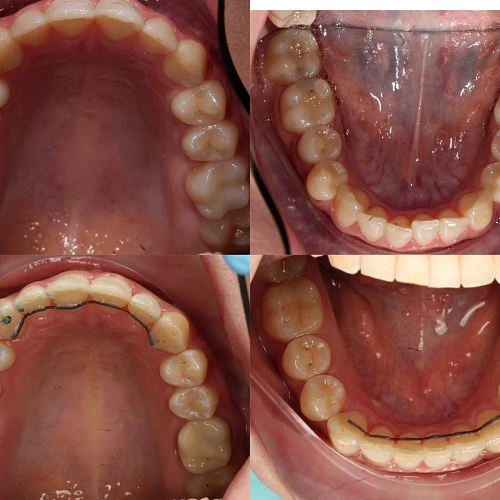

Обе челюсти сужены — зубам не хватало места, они стояли скученно на верхней и нижней челюсти. Нарушена кривая смыкания — жевательные зубы были на разной высоте.

Зубы выровнены, скученность устранена, линия смыкания нормализована. Установлены несъёмные ретейнеры на обе челюсти, сняты слепки для ретенционных кап.

Проблема: Пациентка живёт за рубежом и обратилась с жалобами на неровные зубы. При осмотре обнаружили сужение обеих челюстей, скученность на верхней и нижней, а также деформацию кривой смыкания — жевательные зубы стояли на разной высоте, из-за чего нагрузка при еде распределялась неравномерно. Дополнительная сложность — пациентка не могла приезжать на визиты часто.

Решение: Поставили элайнеры Click на обе челюсти. Начали с 32 кап, но случай потребовал три дозаказа: 30, 10 и 10 кап — итого 82 капы за 30 месяцев. Количество дозаказов объясняется и сложностью случая (скученность плюс деформация кривой Шпее), и тем, что контрольные визиты были реже обычного из-за проживания за границей. Тем не менее результат достигнут: зубы ровные, смыкание в норме. На ретенцию пациентка приехала отдельно — зафиксировали ретейнеры на обе челюсти, сняли слепки для ретенционных кап.

Сложный случай: скученность на обеих челюстях плюс деформация кривой Шпее — жевательные зубы на разной высоте. Дополнительный вызов — пациентка живёт за рубежом, визиты реже, контроль сложнее. Три дозаказа — много, но каждый был обоснован: основной набор расширил дуги и убрал основную скученность, дозаказы последовательно довели смыкание до нормы. 82 капы за 30 месяцев — результат получен.